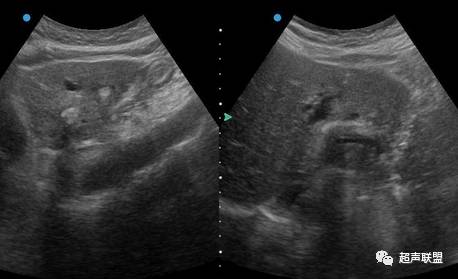

B超诊断

B超为无创性检查,方便易行,是肝内胆管结石诊断的首选方法,一般估计诊断准确率为50%-70%。肝内胆管结石的超声图象变化较多,一般要求在结石远端的胆管有扩张才能作出肝内胆管结石的诊断,因肝内管道系统的钙化也具有结石样的影像表现。

肝内胆管结石的诊断不受肠道气体的干扰,诊断的准确性优于肝外胆管结石。诊断正确率70%~80%。但肝内胆管分支较多,不仔细扫描易漏诊,而且还要与肝内钙化点相鉴别。B超对肝内钙化点与肝内胆管结石鉴别困难在于,如果肝内点状、团状回声,其后若有声影,并不是典型的条索状回声,其后拽有声影,那么单纯依靠B超诊断肝内胆管结石比较困难。应结合其它手段综合判断。

B超诊断肝内胆管结石典型的图像是条索状回声,其后拽有声影,其远端胆管明显扩张,可为结石引起的胆道梗阻及并发的胆管狭窄所致。有报道术中B超的应用(术中于肝脏面、膈面全面超声扫描)可提高肝内胆管结石的诊断率达91%,残石率降至9%。

总结重点:肝内胆管结石和钙化灶的重点区别

一般要求在结石远端的胆管有扩张才能作出肝内胆管结石的诊断,因肝内管道系统的钙化也具有结石样的影像表现。